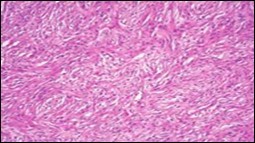

Figure 1.Soft tissue perineurioma with fascicles of bipolar neural cells with elongated cytoplasmic processes, wavy nuclei and an admixture of collagen fibres 11.

Figure 2.Soft tissue perineurioma with lamellar bundles of neural cells demonstrating elongated cytoplasmic processes, wavy, slender nuclei and admixed collagen fibres 12.

Figure 3.Soft tissue perineurioma with whorls and fascicles of neural cells displaying wavy nuclei, elongated cytoplasmic fibrils and intermingling of collagen fibres 13.

Figure 4.Soft tissue perineurioma composed of whorls and perivascular aggregates of neural cells with bipolar cytoplasmic processes, wavy, slender nuclei and commingled collagen fibres 13.

Figure 5.Soft tissue perineurioma /schwannoma with whorls and lamellae of neural cells with bipolar cytoplasmic processes, wavy nuclei and intermingled collagen fibres 14.

Figure 6.Soft tissue perineurioma with foci of spindle cells with wavy nuclei and an admixture of myxoid and collagenous stroma 15.

Figure 7.Soft tissue perineurioma with an abundance of collagen fibrils intermixed with a neural element with bipolar cells with elongated cytoplasm and wavy nuclei 16.

Figure 8.Soft tissue perineurioma with neural cells exemplifying elongated cytoplasmic processes, slender, wavy nuclei and an abundance of collagenous stroma 17.

Figure 9.Soft tissue perineurioma with plentiful collagenous fibrils intermixed with lamellar neural tissue with elongated cytoplasmic extensions and wavy, pointed nuclei 18.

Figure 10.Soft tissue perineurioma demonstrating immune reactivity to epithelial membrane antigen EMA18.

Figure 11.Soft tissue perineurioma with whorls of neural cells delineating spindle cells with bipolar cytoplasm and wavy nuclei and an admixture of collagen bundles 19.